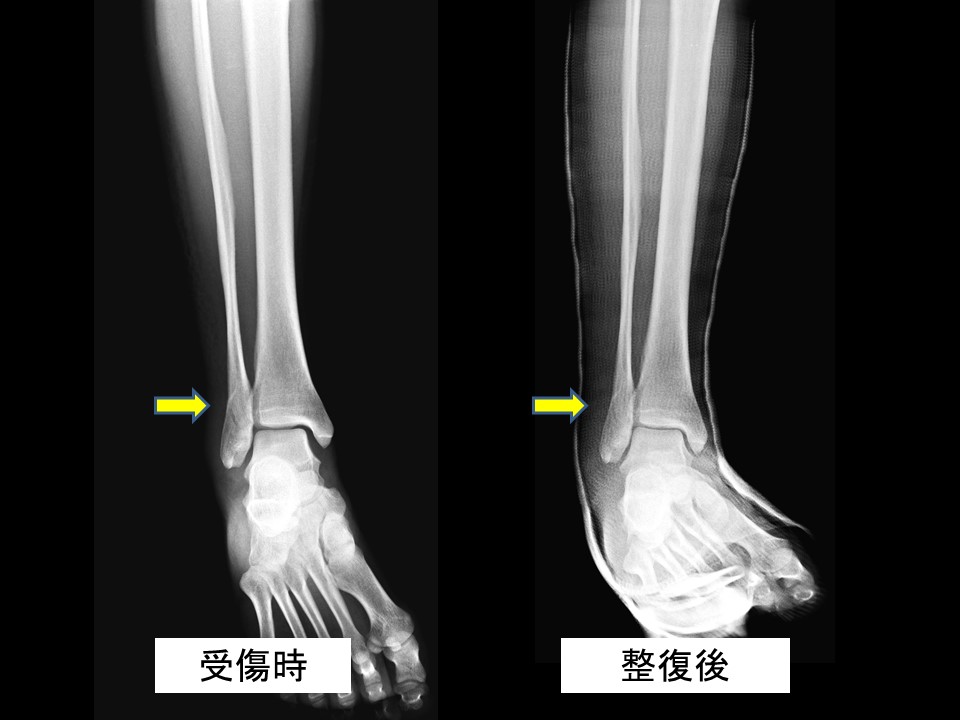

子供さんの足首の骨折

子供さんの足首の骨折

子供さんの足首の骨折

腓骨遠位骨端線損傷 小児の骨折と成人の骨折ではどう違うの 古東整形外科 リウマチ科

子どもの足首捻挫 長引く腫れや痛み はく離骨折疑って 朝日新聞デジタル